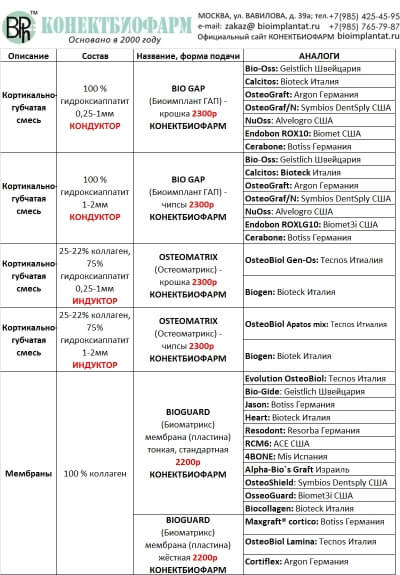

Сравнительная таблица остеопластических материалов